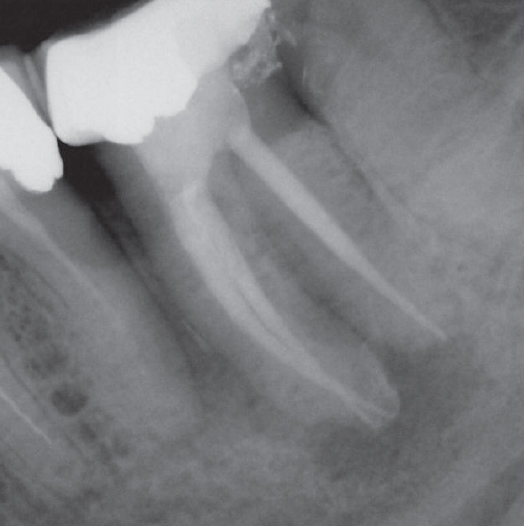

After

After Root Canal treatment